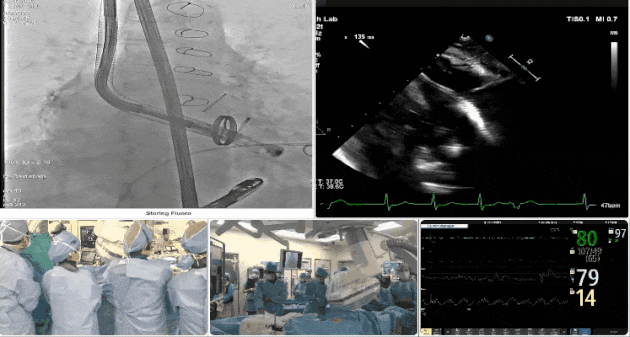

術后DSA、超聲顯示人工瓣膜穩(wěn)定性良好,瓣葉啟閉正常,無瓣周漏

術中TEE觀察夾持件的位置

術后DSA